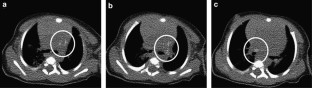

We report a very rare case of isolated multiple pulmonary arterial calcification with severe bilateral peripheral pulmonary arterial stenosis diagnosed in utero. Despite treatment with bisphosphonate for 6 months, systolic right ventricular pressure increased persistently and surpassed left ventricular pressure. After successful bilateral pulmonary arterioplasty at 13 months of age, the patient showed decreased systolic right ventricular pressure with normal interventricular septal configuration. This is the first case report for an isolated pulmonary artery calcification without other arterial calcification proven by non-contrast computed tomography of a living patient.